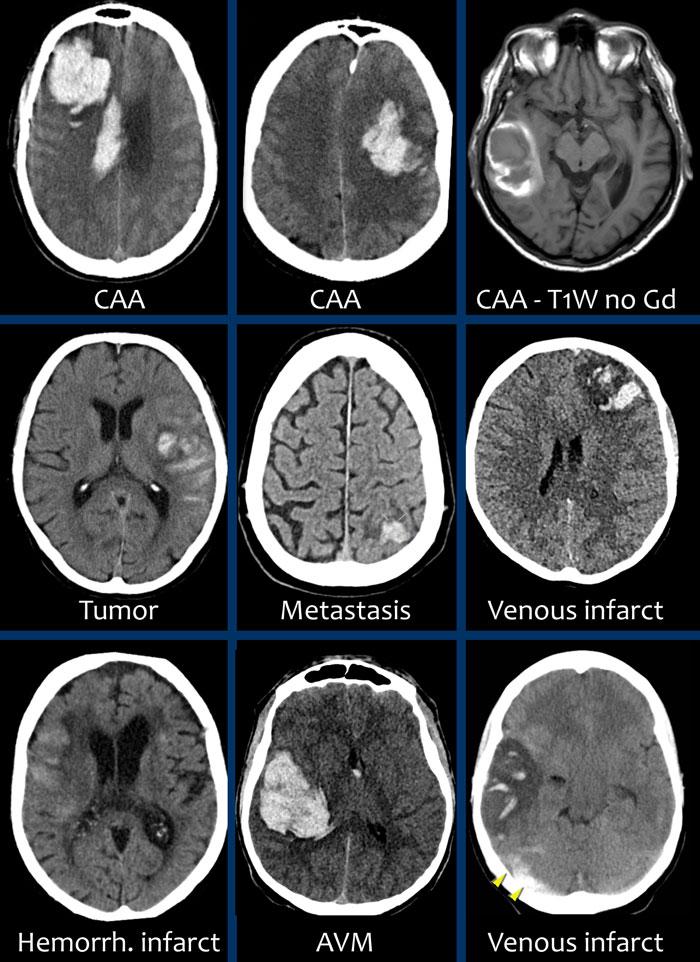

- Tụ máu thùy não nằm ở ngoại vi của một thùy não. Nguyên nhân phổ biến nhất là bệnh lý mạch máu não dạng bột (cerebral amyloid angiopathy), nhưng cũng có thể gặp trong tăng huyết áp, u não, dị dạng mạch máu, nhồi máu tĩnh mạch và nhiều bệnh lý khác.

- Xuất huyết vị trí trung tâm tại hạch nền, cầu não hoặc tiểu não. Nguyên nhân phổ biến nhất là tăng huyết áp.

85% các trường hợp xuất huyết không do chấn thương được ghi nhận ở bệnh nhân có tăng huyết áp hoặc bệnh lý mạch máu não dạng bột (CAA).

Trong tăng huyết áp, xuất huyết thường ở vị trí trung tâm tại hạch nền, cầu não, đồi thị và tiểu não, trong khi trong CAA, xuất huyết thường ở vị trí ngoại vi hơn – sâu trong các thùy trán, đỉnh hoặc thái dương – còn được gọi là xuất huyết thùy não.

Xuất huyết thùy não

Xuất huyết thùy não nằm ở ngoại vi của các thùy đại não, khác với xuất huyết do tăng huyết áp thường nằm ở vị trí trung tâm hơn.

Nguyên nhân phổ biến nhất, đặc biệt ở người cao tuổi, là bệnh lý mạch máu não dạng bột, nhưng tăng huyết áp cũng thường gặp do tỷ lệ mắc cao.

Các nguyên nhân khác:

- U não hoặc di căn có xuất huyết

- Dị dạng mạch hang

- AVM

- dAVF

- Nhồi máu tĩnh mạch

Dưới đây là một số ví dụ về xuất huyết thùy não.

Bệnh lý mạch máu não dạng tinh bột (CAA)

Bệnh lý mạch máu não dạng tinh bột (CAA) là một rối loạn đặc trưng bởi sự lắng đọng chất tinh bột (amyloid) trong thành các động mạch nhỏ màng mềm não và vỏ não, dẫn đến bệnh lý chất trắng não và xuất huyết.

Các ổ xuất huyết có thể được phân loại thành xuất huyết lớn (macrobleeds) hay xuất huyết thùy, xuất huyết vi thể (microbleeds) và xuất huyết dưới nhện gây ra tình trạng nhiễm sắt bề mặt vỏ não (cortical superficial siderosis).

Xuất huyết nội sọ do tăng huyết áp cùng với CAA chiếm 80% nguyên nhân gây khối máu tụ trong nhu mô não.

Cần nghĩ đến CAA khi phát hiện nhiều ổ xuất huyết ngoại vi hoặc xuất huyết thùy ở bệnh nhân cao tuổi.